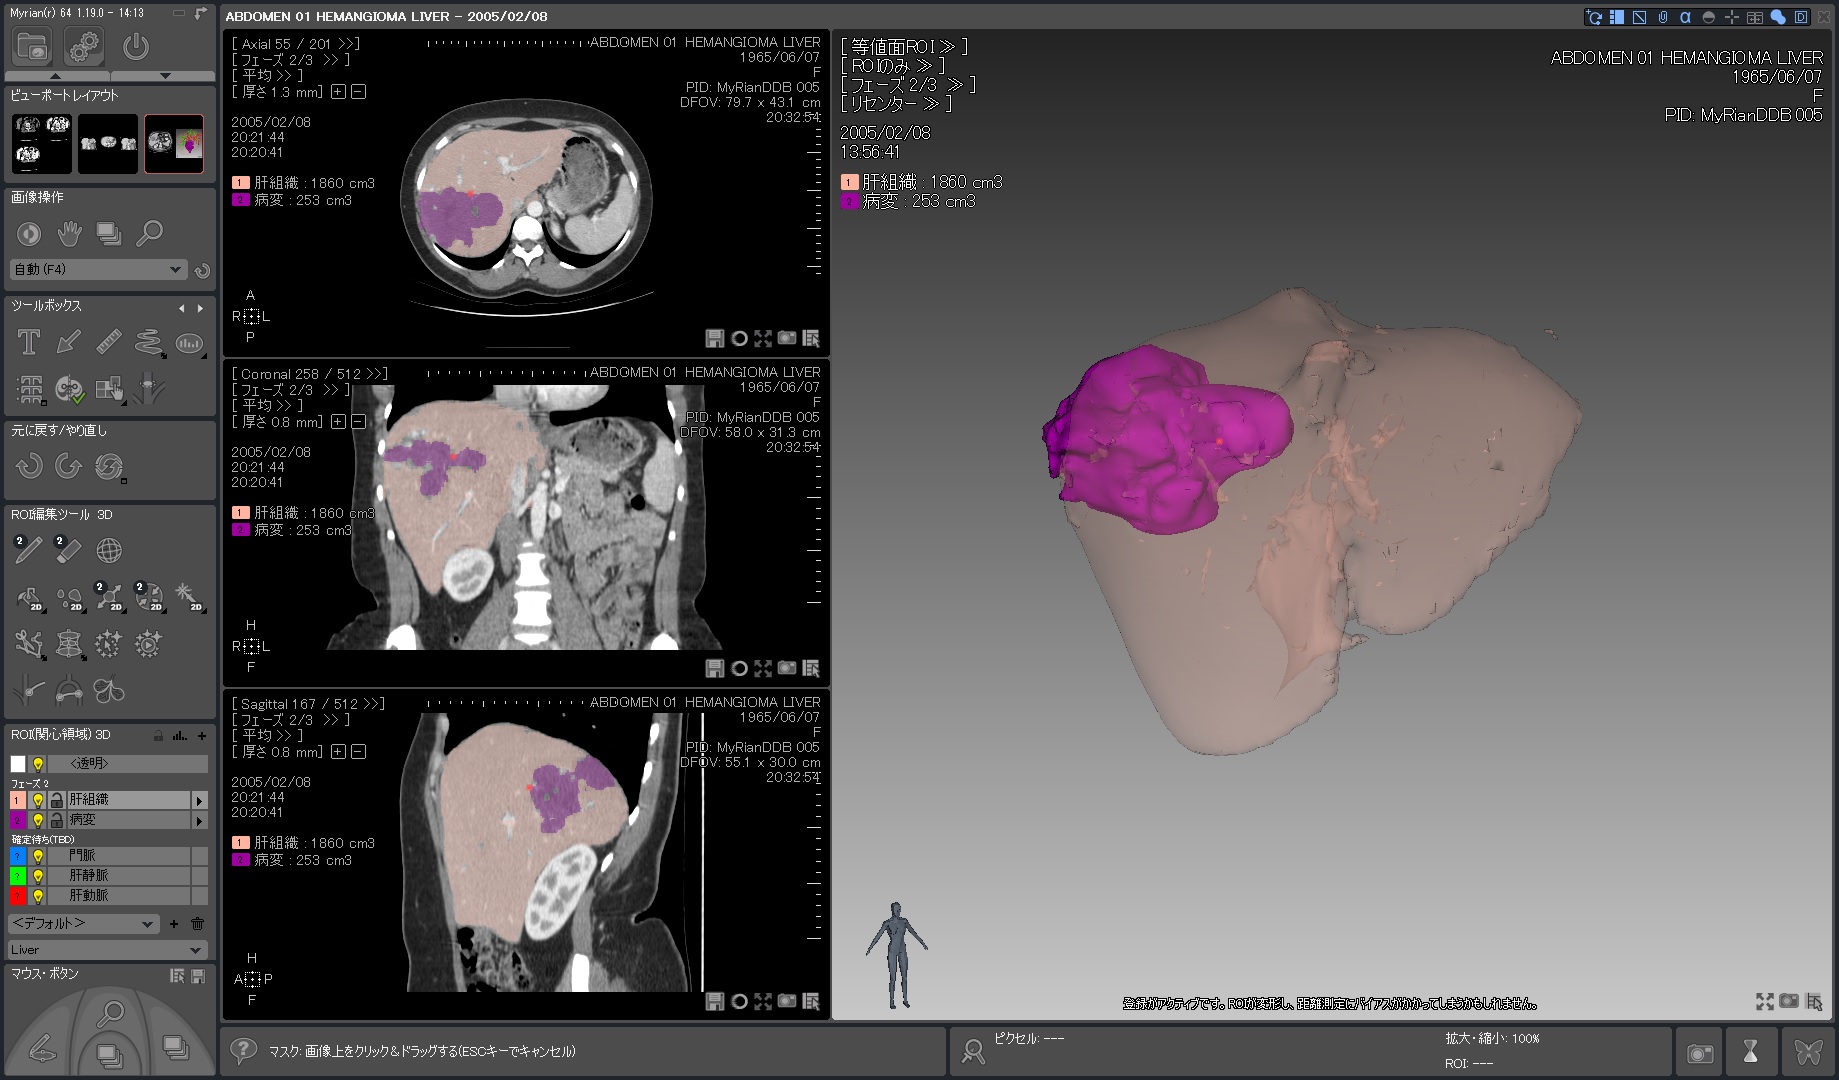

Myrian®XP-Liver 肝臓アプリケーション

世界的な実績と評価を得ている、肝臓解析と手術計画用ソフトウェア

独自に開発された、正確な非剛体レジストレーションと優れたセグメンテーション・アルゴリズムにより肝血管系、肝実質、腫瘍などを数秒で抽出します。

3D PDFによる立体表示ではコミュニケーションの向上に寄与するでしょう。

当製品は3D業界の先駆けとして、世界トップの施設で使用されています。

| 1.病変部領域 正常部領域の ワンクリック セグメンテーションと 体積表示 |

|

|---|---|